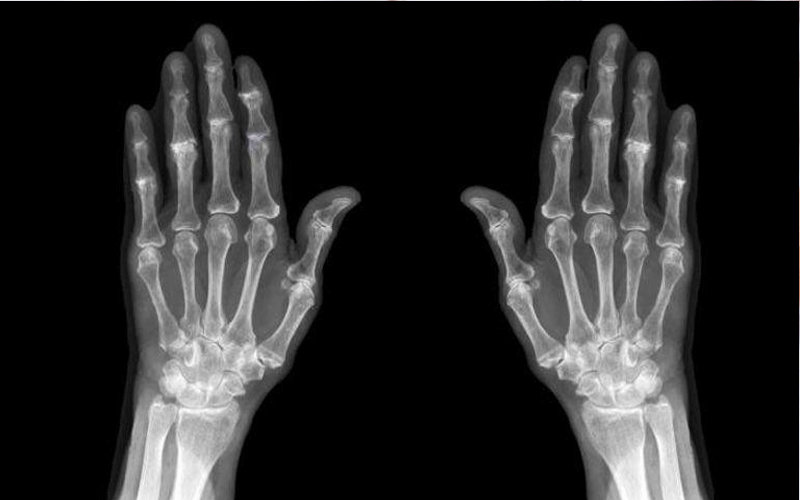

نيسان ـ يعد فقدان العظام جزءًا طبيعيًا من الشيخوخة لكن بعض الأشخاص يعانون من هشاشة العظام بشكل أسرع من المعتاد وفي سن صغيرة .. فما السبب؟

ووفقا لما جاء موقع “ NHS” يمكن أن يؤثر مرض هشاشة العظام على الرجال والنساء الأصغر سنًا والأطفال وتؤدي العديد من العوامل الأخرى لزيادة الإصابة بالمرض.